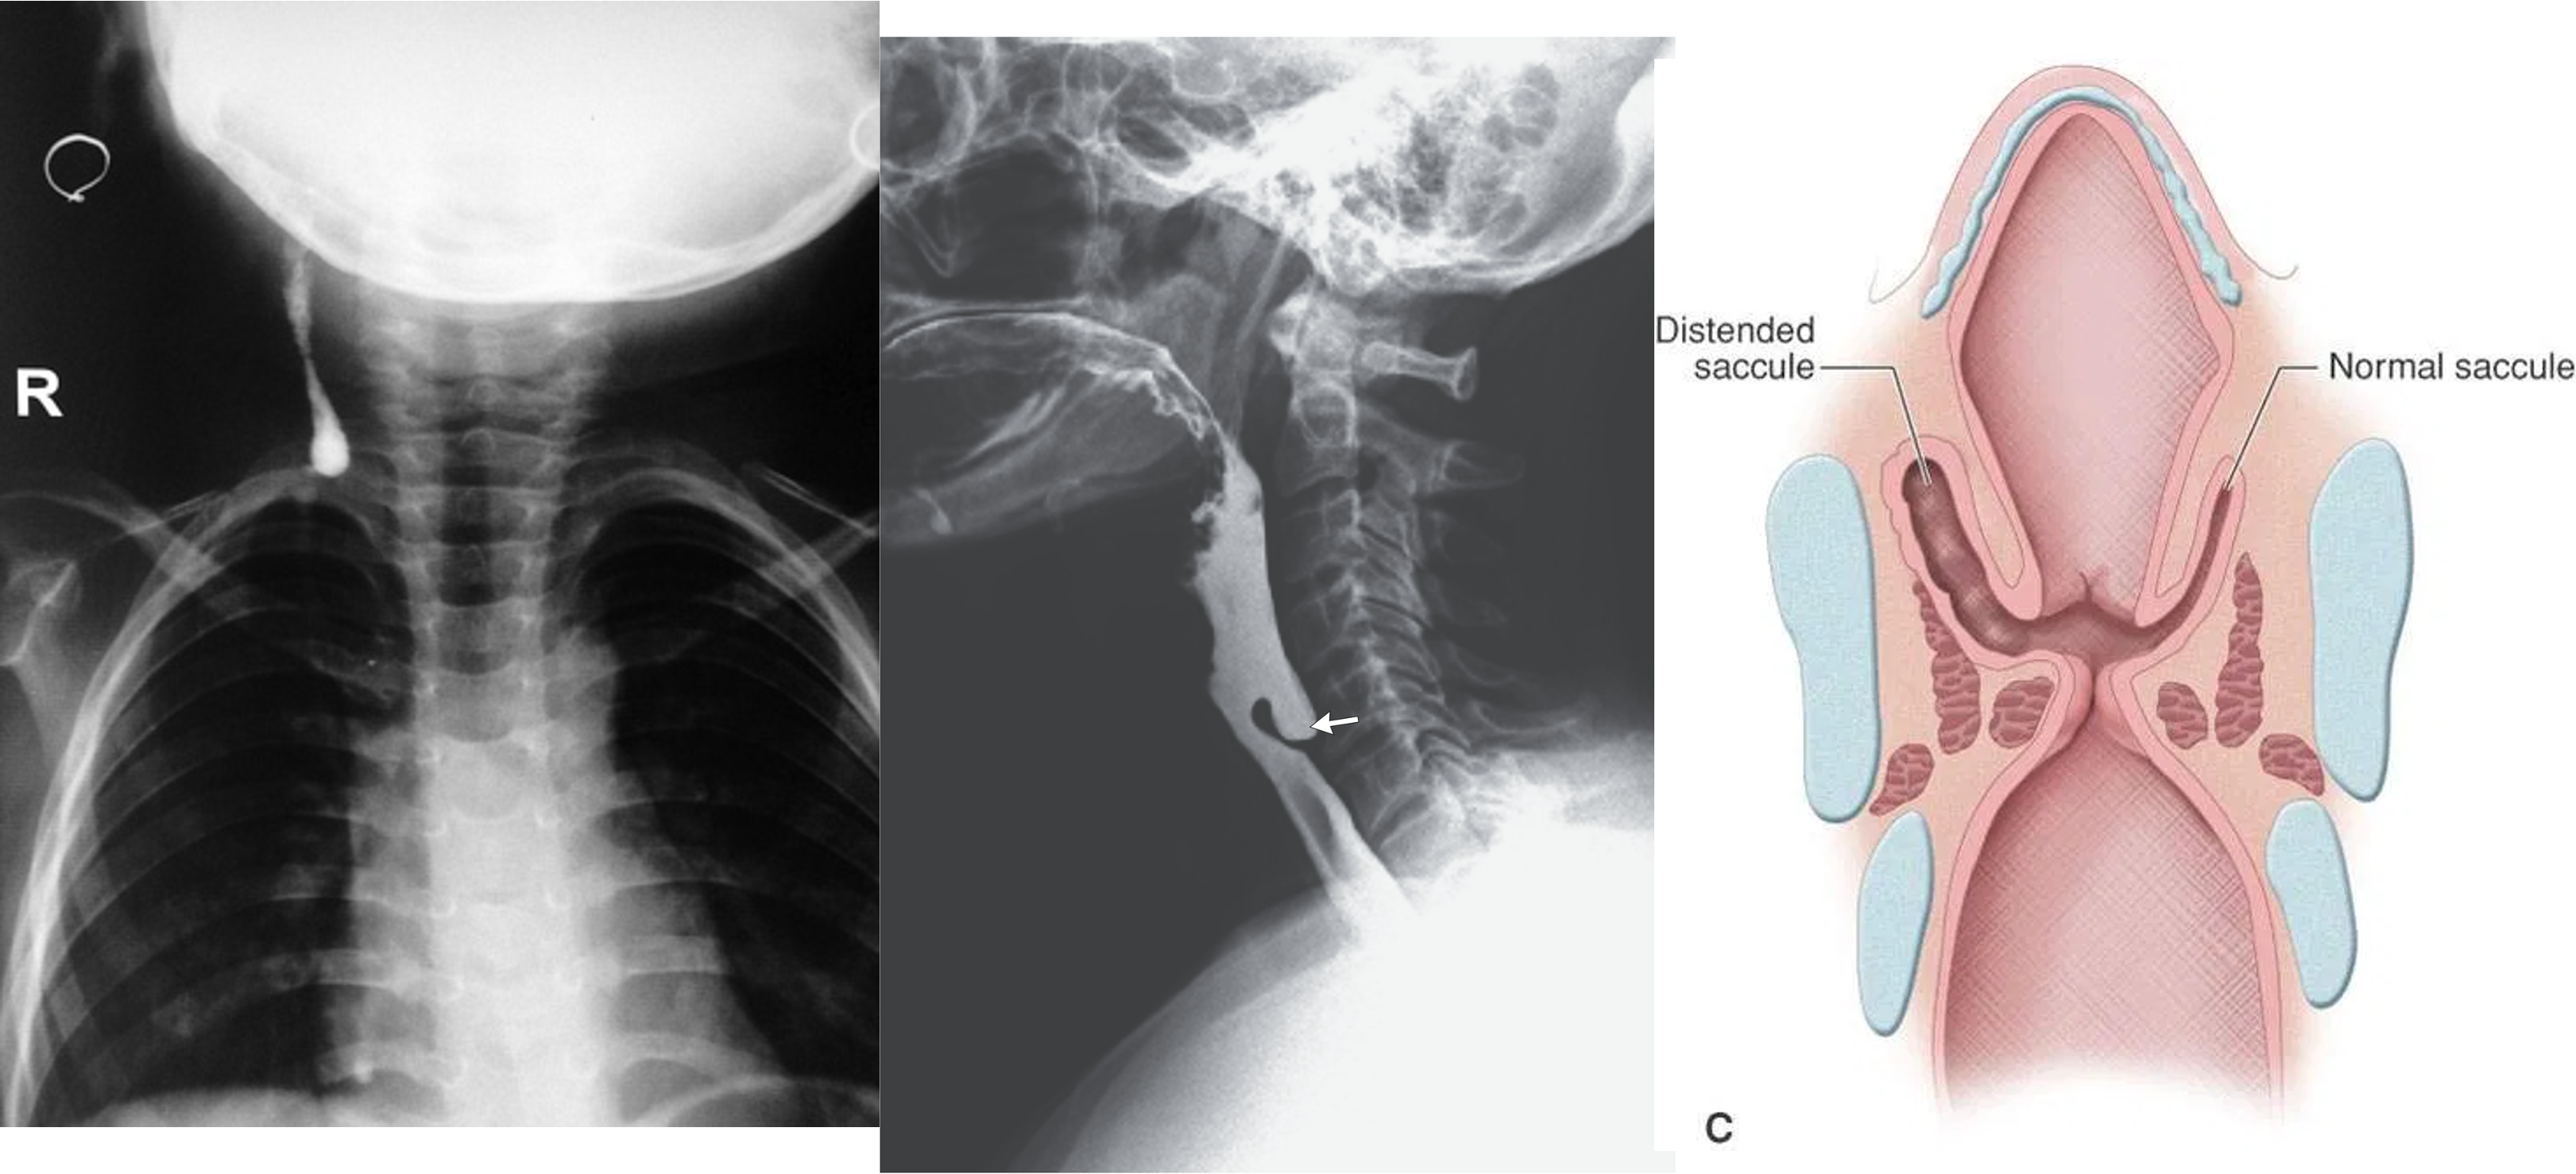

1,2,3- valsava maneuvear - laryngocele